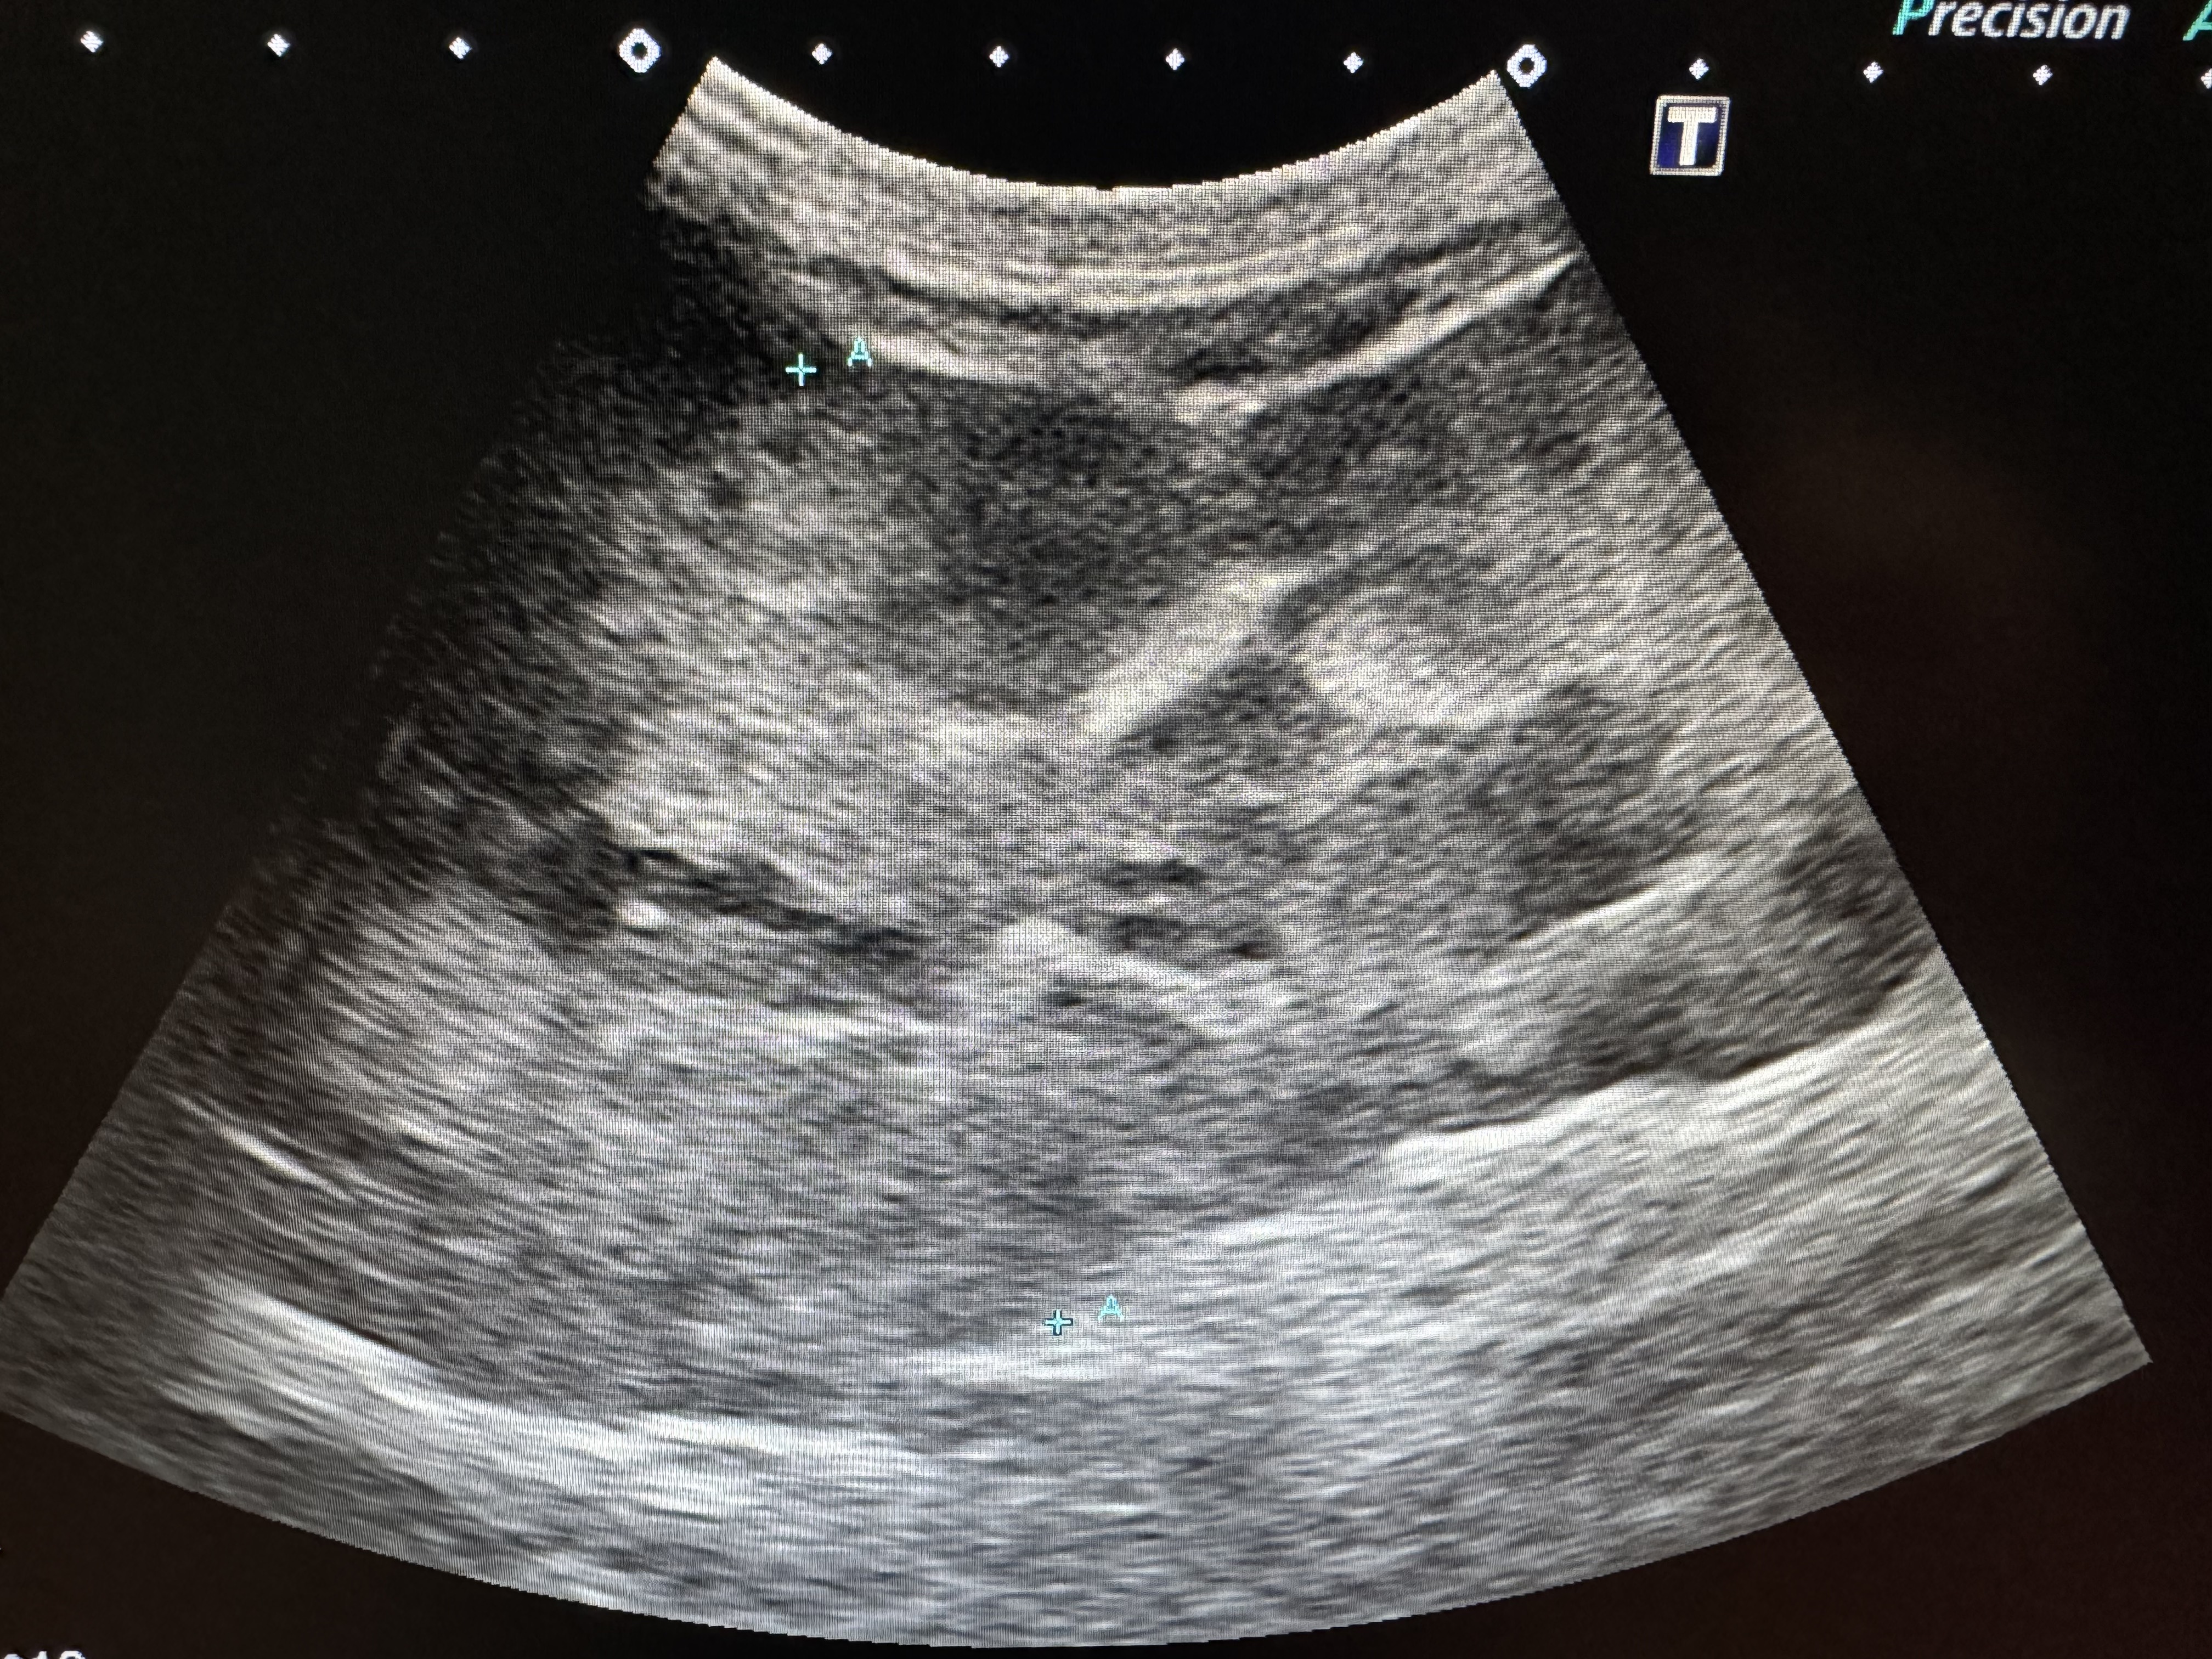

4. 超音波検査(腫瘍の大きさ・破裂有無・腹水確認)

脾臓腫瘍の超音波検査画像です。この腫瘍では、腹部に普通認められない混合エコー性の大きなマス病変(肉の塊)が確認され、時に出血を伴う腹水が認められることがあります。緊急の手術が必要になることが多いです。